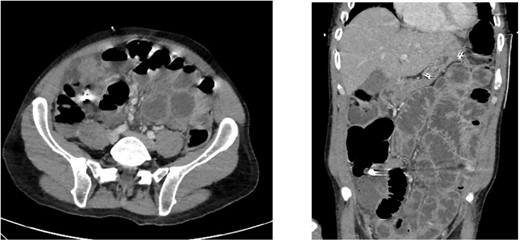

A 52-year-old gentleman who presented to the Emergency Department in septic shock with right sided abdominal pain. He suffered a witnessed cardiac arrest prompting immediate cardiopulmonary resuscitation (CPR) with return of spontaneous circulation (ROSC) after 10 minutes. Physiologic resuscitation was commenced, and he was started on broad spectrum intravenous antibiotics with cefuroxime and metronidazole, as per local guidelines. Following intubation and ventilation, he underwent a computer tomography (CT) scan of the abdomen which revealed moderate volume of free fluid with locules of gas within the pelvis suggesting a hollow viscus perforation. A calcified structure was identified within the appendix raising the possibility of a foreign body causing perforated appendicitis. On reconstructed slices, the appearance was that of a tooth (Figs 1 and 2).

Axial and coronal CT slices showing radiopaque object in the right lower abdominal quadrant.